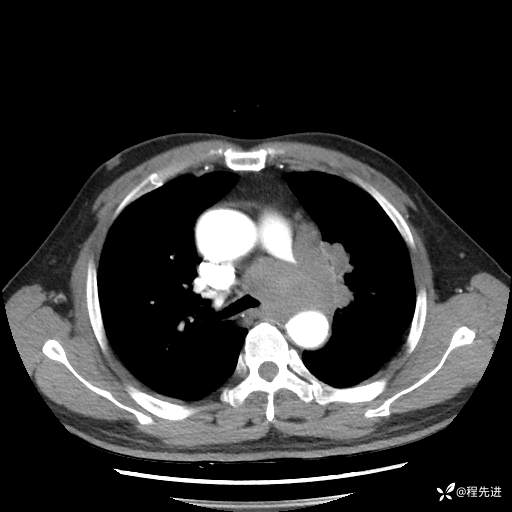

患者性别:男

患者年龄:57岁

简要病史:声嘶2月余

CT平扫+增强: